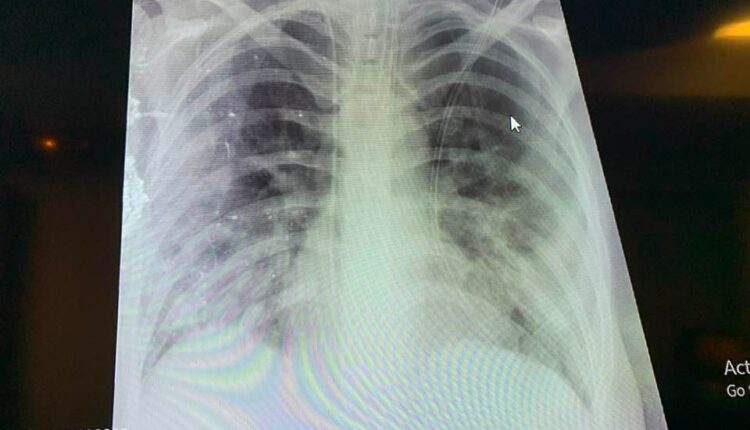

Σοκαριστική είναι η ακτινογραφία του πνεύμονά της που δημοσιοποίησε στο Facebook ο Καθηγητής Παιδιατρικής του ΑΠΘ, Κοσμάς Σαραφίδης, από το Ιπποκράτειο Θεσσαλονίκης.

Μόνο ο μισός από τον κάθε πνεύμονά της λειτουργεί και η πρόγνωση για την εξέλιξη της κατάστασης της υγείας της είναι άγνωστη. Η εικόνα της ακτινογραφίας που ανάρτησε ο Παιδίατρος είναι χαρακτηριστική:

Ακτινογραφία θώρακα ανεμβολίαστης εγκύου που διασωληνώθηκε χτες και γέννησε πολύ πρόωρα λόγω της βαρύτητας της κατάστασης της. Μόνο ο μισός από τον κάθε πνεύμονα της λειτουργεί. Άγνωστη η πρόγνωση της μητέρας.